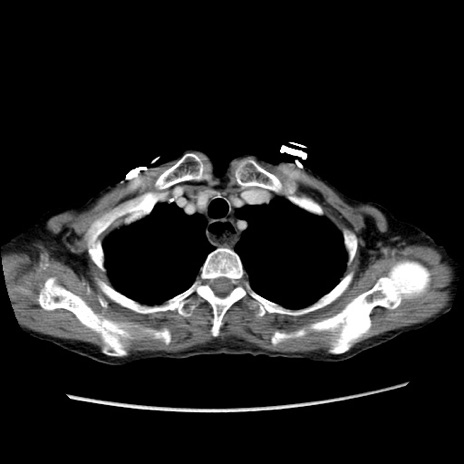

冠状断像

症例25(横断像)

【症例】80歳代女性

【主訴】胸のつかえ感

【現病歴】約9時間前に食後から胸のつかえた感じあり、嘔吐あり、来院。

【既往歴】胃癌(全摘)、胆摘、虫垂炎

【身体所見】心窩部に圧痛あり、反跳痛なし。

【データ】WBC 5700、CRP 0.05